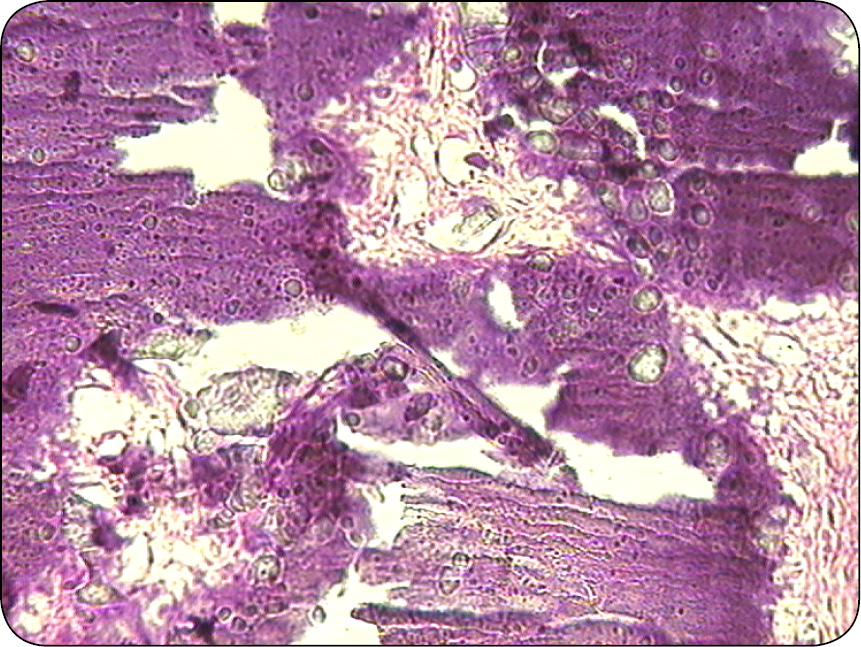

Jest guzem wywodzącym się z komórek macierzy włosa. Zbudowany z licznych torbieli, których zawartość ulega inkrustacji solami wapnia. Ściana torbieli jest zbudowana z kilku warstw komórek, które ulegają zwyrodnieniu i nekrobiozie, wypełniają światło torbieli (ryc. 9). W świetle torbieli znajduje się homogenna eozynochłonna masa, w której są widoczne cienie komórkowe (ryc. 10). Stąd wywodzi się angielskie określenie „cieni komórkowych” – shadow cells. Cechą charakterystyczną tych guzów jest wapnienie obumarłych komórek obecnych w świetle torbieli (ryc. 11).